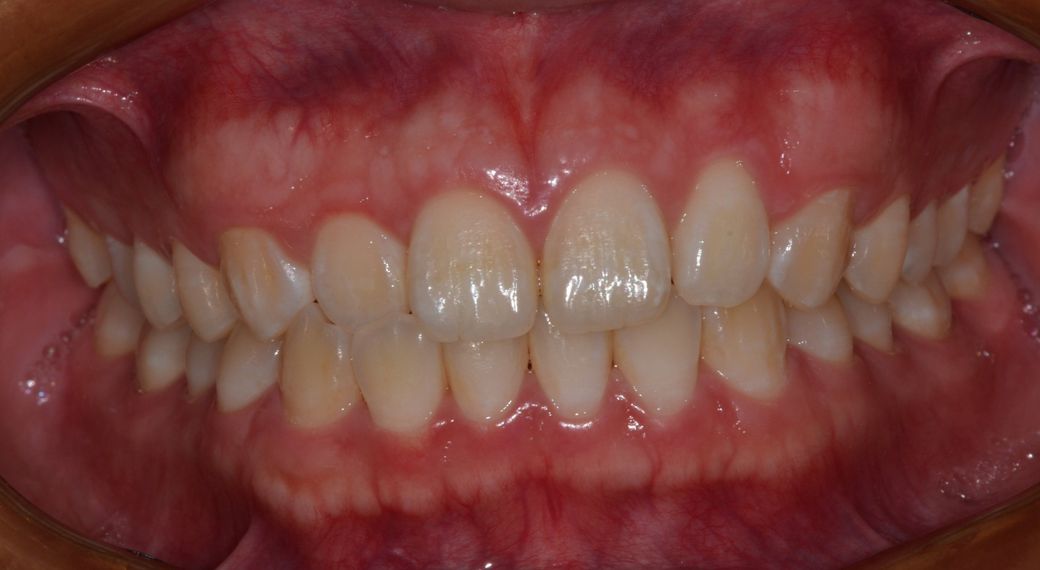

교정치과에서 교정시 앞니치아 조기상실 가능성있다고 하는데

돌출입 교정 상담 받았는데 치과에서 앞니 치근이 짧다고 발치 교정은 추천하지 않으며 또한

비발치 전체 교정으로 사랑니 공간으로 치아전체 후방이동 또한 무리일 것 같다고 합니다

원하는 결과를 얻기에는 교정보다는 양악수술 쪽을 고려해 봐야 한다고 했습니다

하지만 굳이 무리하게 무엇인가를 하기보다는 앞니 측철치 절단교합 치료를 위한 인비절라인 투명교정 또는 앞니 부분 교정정도만 하라고 추천해주셨습니다.

제가 원하는 것은 비발치 전체 교정으로 치아전체 후방이동 이었는데 무리이고 원하는 결과를 얻기 힘들거라고 해서 고민입니다

교정 자체를 하는 것이 심미적인 목적이라면 지금 상태에서는 양악을 하는 것이 맞습니다. 치근단이 짧을 경우에는 치근 흡수 등이 일어나면 돌이킬 수 없는 결과로 이어질 수 있습니다. 다만 현재 안모 사진으로 보았을 때는 교정을 하지 않더라도 기능적인 부분은 전혀 문제가 없을 것으로 보입니다.